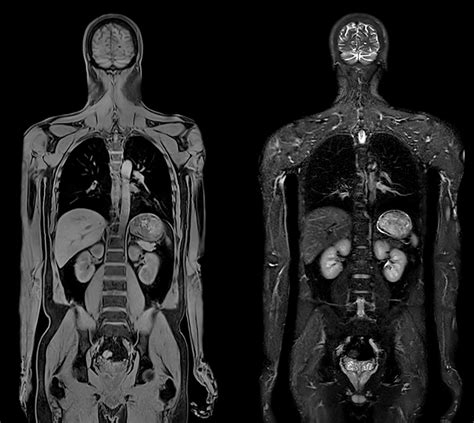

Steriletul Mirena și RMN-ul

Un dispozitiv intrauterin tip sterilet este un dispozitiv mic, în forma de T, pe care un medic ginecolog îl poate implanta in uter pentru a preveni sarcina. Nu fac parte din categoria pacienților pentru care examinarea RMN este contraindicată, pacientele care au un sterilet inserat, ele putând oricând să beneficieze de RMN.

Investigația în sine se imparte în trei etape: Examinarea nativă - obținerea de imagini fără a utiliza medicamente sau substanțe; Examinarea cu substanță de contrast - prin intermediul unei branule, este injectată în sistemul circulator o substanță de contrast, care permite vizualizarea cât mai clară a zonelor de interes; Instilarea de gel la nivel vaginal și rectal, în vederea destinderii pereților vaginali și rectali. Acest lucru permite obținerea unor imagini cât mai precise ale zonei pelvine.

Perioada cea mai avantajoasă pentru efectuarea unui RMN de pelvis cu protocol de endometrioza este intervalul dintre sângerările menstruale, când vizibilitatea este optimă. Există, totuși, situații când acest lucru nu este posibil (de exemplu, în cazul pacientelor care au sângerări intermenstruale sau menstruații prelungite), însă examinarea RMN nu este contraindicată.